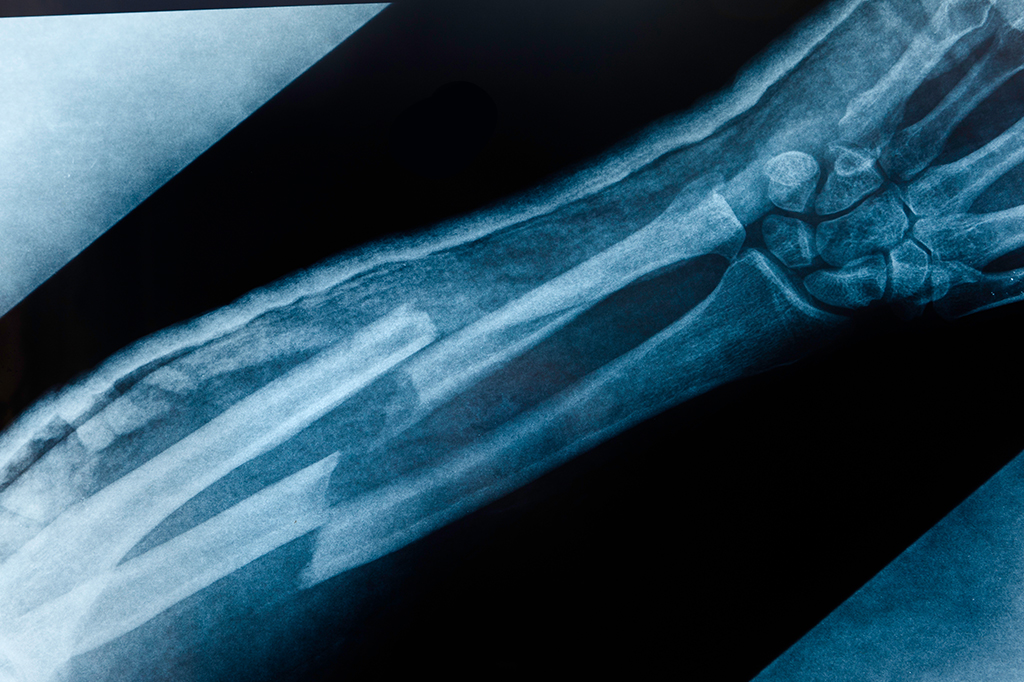

Tudo sobre FRATURA

Como um osso quebrado se regenera?